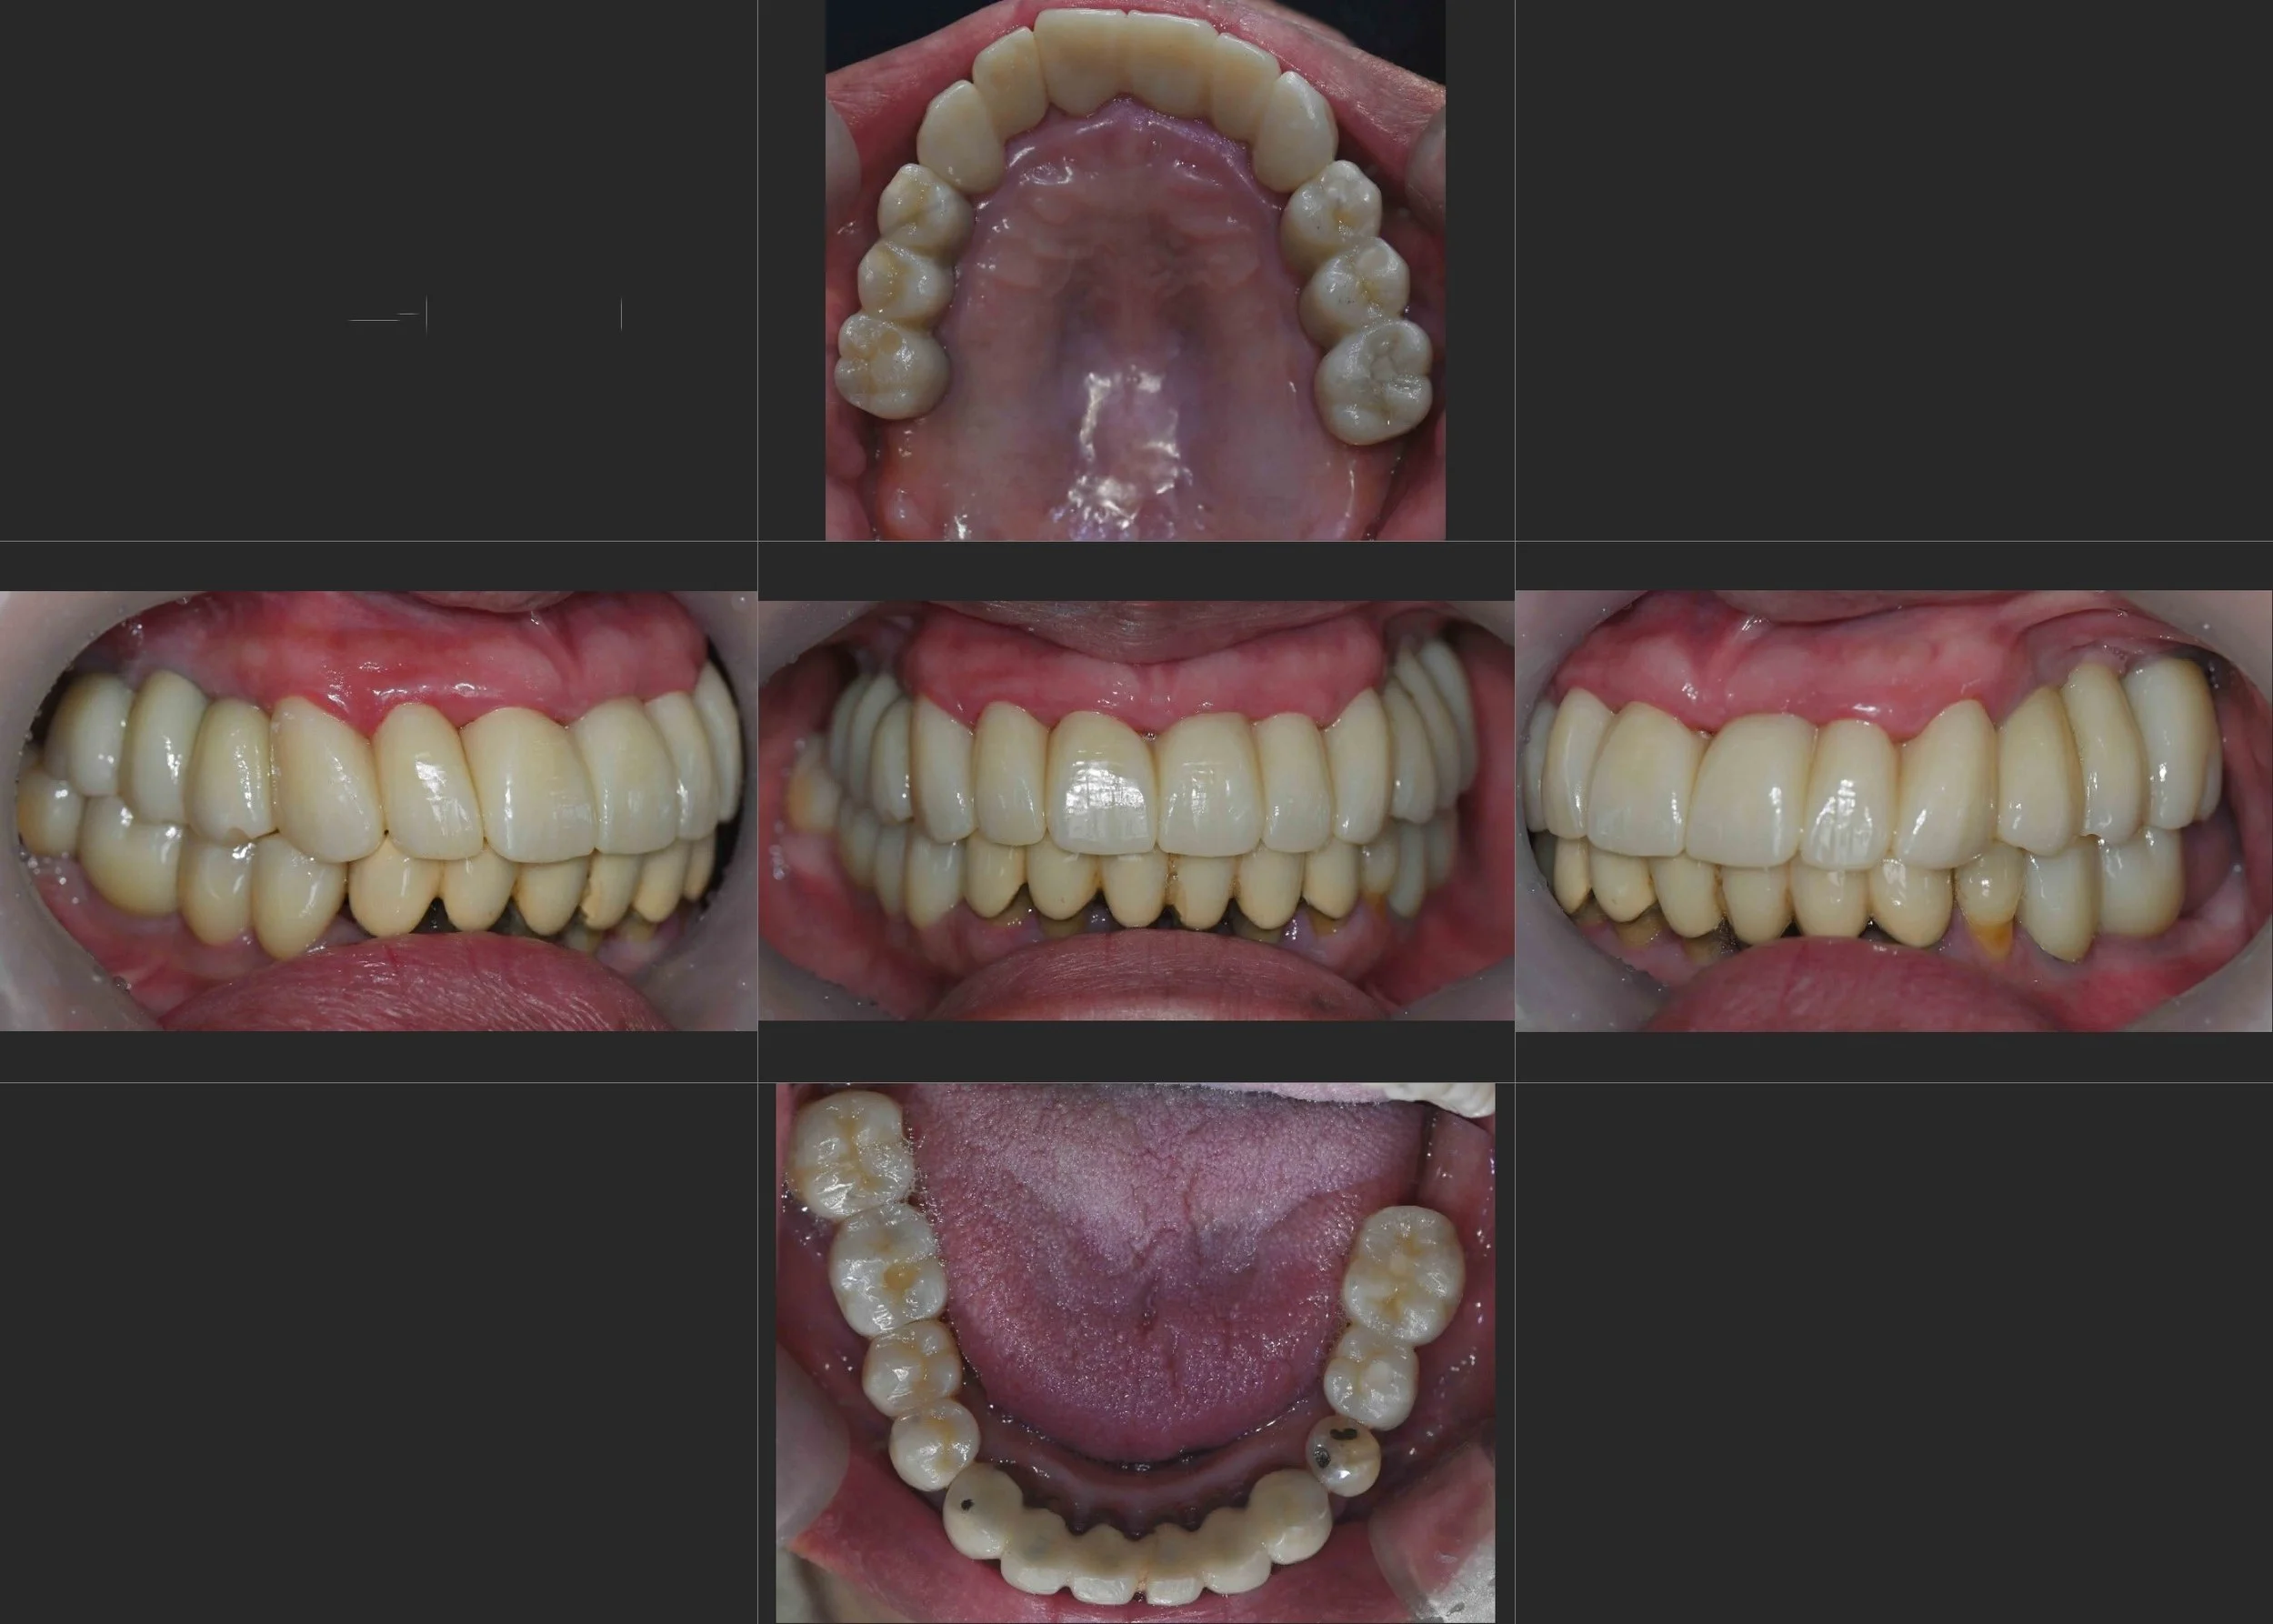

INTRA ORAL - AFTER